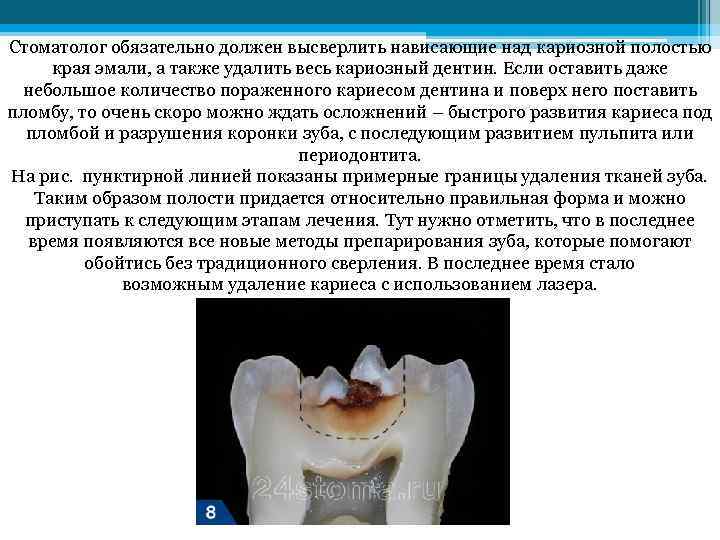

Стоматолог обязательно должен высверлить нависающие над кариозной полостью края эмали, а также удалить весь кариозный дентин. Если оставить даже небольшое количество пораженного кариесом дентина и поверх него поставить пломбу, то очень скоро можно ждать осложнений – быстрого развития кариеса под пломбой и разрушения коронки зуба, с последующим развитием пульпита или периодонтита. На рис. пунктирной линией показаны примерные границы удаления тканей зуба. Таким образом полости придается относительно правильная форма и можно приступать к следующим этапам лечения. Тут нужно отметить, что в последнее время появляются все новые методы препарирования зуба, которые помогают обойтись без традиционного сверления. В последнее время стало возможным удаление кариеса с использованием лазера.

Стоматолог обязательно должен высверлить нависающие над кариозной полостью края эмали, а также удалить весь кариозный дентин. Если оставить даже небольшое количество пораженного кариесом дентина и поверх него поставить пломбу, то очень скоро можно ждать осложнений – быстрого развития кариеса под пломбой и разрушения коронки зуба, с последующим развитием пульпита или периодонтита. На рис. пунктирной линией показаны примерные границы удаления тканей зуба. Таким образом полости придается относительно правильная форма и можно приступать к следующим этапам лечения. Тут нужно отметить, что в последнее время появляются все новые методы препарирования зуба, которые помогают обойтись без традиционного сверления. В последнее время стало возможным удаление кариеса с использованием лазера.